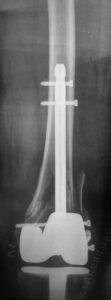

- Σε περιπροθετικά κατάγματα που είναι πολύ περιφερικά (στην άκρη του μηριαίου οστού) και έχουμε υπερήλικα ασθενή χαμηλών δραστηριοτήτων ,μπορούμε να αντικαταστήσουμε ολόκληρο το περιφερικό μηριαίο οστούν με ειδικό εμφύτευμα

- Σε σοβαρά περιπροθετικά κατάγματα όπου υπάρχει εκσεσημασμένη απώλεια οστού και αστοχία των προηγούμενων υλικών οστεοσύνθεσης, μπορεί να αντικατασταθεί το μεγαλύτερο μέρος του μηριαίου οστού με ειδική μεγαπρόθεση που θα επιτρέψει άμεση κινητοποίηση στον ασθενή.